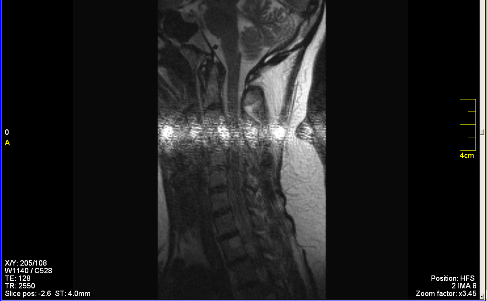

Siemens impact Expert при работе на катушке Шея CP Neck array, периодически на изображении появляется горизонтальная полоса

5602326.png (74.6 Kb)